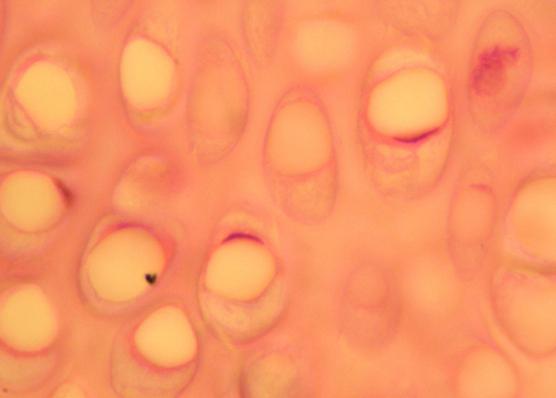

Верхний выстлан клетками, которые имеют название зародышевого эпителия. Под ним находится плотная и эластичная строма. А дальше — паренхима, имеющая в своем составе два слоя. Внутри ее имеется рыхлая субстанция, которая пронизана множеством лимфатических и кровеносных сосудов. Следующий слой — вещество, которое считается инкубатором для фолликулов.

Именно здесь содержаться пузырьки с молодой яйцеклеткой, а также фолликулы, которые находятся в стадии созревания. Созревший фолликул является вполне самостоятельной эндокринной единицей, ведь он вырабатывает гормоны. Каждый пузырек с яйцеклеткой в свое время разрывается, высвобождая ее. На месте пузырька возникает желтое тело.

Яичники локализуются в полости малого таза, не покрытые брюшиной и снаружи окружены одним слоем клеток поверхностного (или зародышевого) эпителия. Основной гормонопродукуючою частью яичников является корковый слой. В нем среди соединительнотканной стромы расположены фолликулы. Основная их масса — примордиальные фолликулы, которые представляют собой яйцеклетку.

В течение периода постнатальной жизни большое количество примордиальных фолликулов гибнет, и до периода половой зрелости число их в корковом слое уменьшается в 5-10 раз. Наряду с примордиальными фолликулами в яичниках содержатся также фолликулы, которые находятся на разных стадиях развития или атрезии, а также желтые и белые тела. Центральную часть яичника занимает мозговой слой, в котором отсутствуют фолликулы. В нем среди

проходят основные кровеносные яичниковые сосуды и нервы. Репродуктивный период жизни характеризуется циклическими изменениями в яичниках, которые обусловливают созревание фолликулов, их разрыв с выходом созревшей яйцеклетки (овуляция), образование желтого тела с его последующей инволюцией на случай отсутствия наступления беременности.